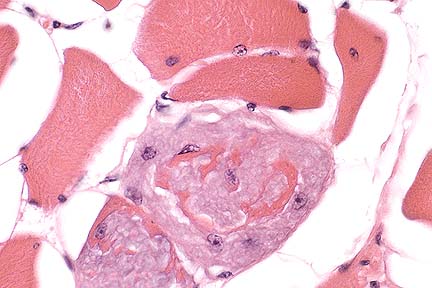

Marked reticuloendothelial hyperplasia in a turkey with adenoviral splenitis. Note the absence of detectable lymphoid elements. (HE, 100X, 86K)

Laboratory Results: Large numbers of Escherichia coli were recovered from blood filtering organs. Transmission electron microscopy (TEM) of spleen confirmed the presence of intranuclear adenoviral particles, 80 nm in diameter, within cells. These virions are widely scattered throughout the enlarged nuclei. There is margination of chromatin.

Morphologic Diagnosis: Moderate acute lymphocytolysis, reticular cell and macrophage hyperplasia with intranuclear viral inclusions, mild multifocal acute splenic fibrinous necrosis, splenic heterophilia.

AFIP Diagnosis: Spleen: Lymphoid depletion and necrosis, diffuse, severe, with reticuloendothelial cell hyperplasia and eosinophilic to amphophilic intranuclear inclusion bodies, turkey, avian, etiology consistent with adenovirus.

Hemorrhagic enteritis virus is transmitted by the fecal-oral route and has been recovered from contaminated bedding. Transmission through the egg is not believed to occur. Generally, poults 4 weeks or older are affected. Gross lesions consist of pale tissues due to anemia, blood-filled intestines, congestion of the intestinal mucosa and lungs, and splenomegaly. Histologically, there is severe congestion of the intestinal mucosa, with necrosis and sloughing of epithelial cells at the tips of villi. The lamina propria is infiltrated by macrophages, plasma cells, and heterophils. Lesions are often more pronounced in the duodenum; however, less severe lesions can occur in the proventriculus, gizzard, large intestine, cecum, cecal tonsils, and bursa of Fabricius. Splenic lesions consist of hyperplasia of white pulp and reticuloendothelial cells, as well as necrosis of lymphoid cells. Reticuloendothelial cells often contain intranuclear viral inclusions.